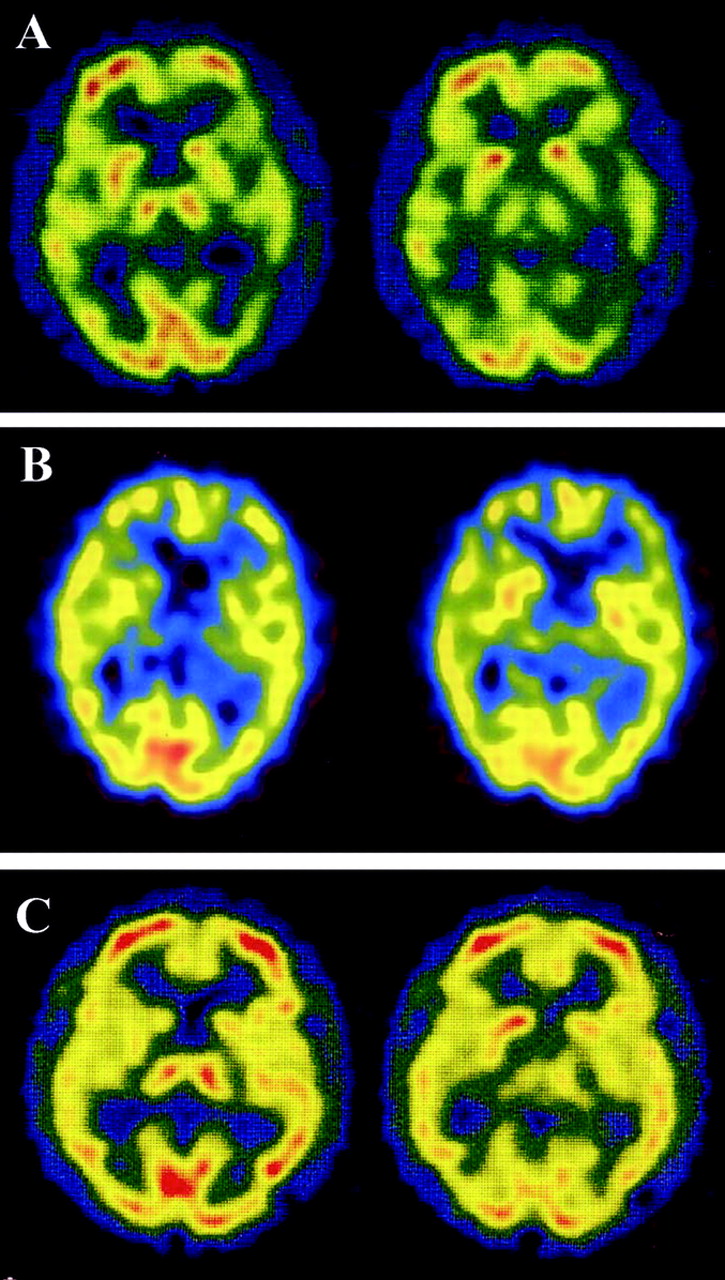

图1所示。大脑核磁共振在16个月后病人2 (A, B)和病人8在7个月后开始(C, D)。A和C是diffusion-weighted成像(驾车),和B和D是fluid-attenuated反转恢复(天赋)成像。在病人2中,酒后驾驶显示hyperintense信号双边额,顶叶、枕叶皮层(A),和天赋成像还显示轻微hyperintensity信号在大脑皮层驾车病变(B)。在病人8中,醉酒驾车和天赋大脑成像显示没有明显的异常信号(C, D)。

图2。SPECT脑血流量(CBF)使用99米Tc-ethyl cysteinate二聚体在16个月后病人2 (A),病人发病8在7个月后(B),和一个正常的控制问题是一个67岁的老人没有神经异常和认知能力衰退(C)。SPECT显示两国在患者的颞叶皮层的CBF减少2 (A)和双边丘脑以及颞叶皮层在病人8 (B)与正常相比控制(C)。

16个月后,MRI显示gyriform hyperintensity双边额叶,颞顶叶和枕叶皮层在diffusion-weighted成像(驾车)(图1一个)。那么激烈,皮质病变显示在小fluid-attenuated反转恢复成像(见图1 b)。脑电图,漫射放缓没有PSWCs被发现。CBF-SPECT使用99米Tc-ECD显示减少的CBF双边顶叶和颞皮层(图2一个)。脑脊液检查发现14-3-3蛋白水平增加(28 ng / mL(正常< 20 ng / mL))。尽管sCJD的临床标准20.并不满足,因为缺乏神经和脑电图异常,怀疑库贾氏症MRI和CSF的基础上发现。

患者1和2的平方毫米皮质出现迟发性的形式,慢慢进步的痴呆(表1)。PSWCs脑电图缺席在早期阶段(表2)。这些特性与之前报道的平方毫米皮质病例。3病人没有完成的临床标准sCJD因为缺乏临床症状。20.重要的是,大脑皮层hyperintensity信号驾车(见表2已报告),这为诊断sCJD是有用的,19日,22日,23日很容易使我们可能库贾氏症的诊断。基底节和丘脑在这些情况下没有hyperintensity核磁共振信号。CSF水平增加(见14-3-3蛋白支持诊断表2)。平方毫米皮质形式经常显示缓慢进行性痴呆没有其他神经系统异常,广告和痴呆与征收机构对鉴别诊断很重要。皮质hyperintensity信号在急性缺血性中风的醉酒驾车被发现,23单纯疱疹脑膜脑炎,22、23创伤后挫伤,22、23postictal变化,22和米拉(线粒体肌病、脑病、乳酸酸中毒和类似中风发作)24;然而,他们并没有观察到广告25或者和路易体痴呆。19我们建议以下为平方毫米皮质sCJD诊断标准:1)进行性痴呆,2)皮质hyperintensity信号在酒后驾驶,和3)脑脊液14-3-3蛋白质含量增加,排斥其他痴呆症,包括其他类型的朊病毒疾病。其他神经精神异常比痴呆或PSWCs脑电图不一定是必需的。

平方毫米的情况下丘脑的形式,发病年龄范围从30到71年,临床过程的持续时间从13到73个月(见表1)。临床表现包括精神病症状,痴呆,小脑性共济失调、失眠、和自主失败(见表1)。至于FFI的突出特点和SFI,失眠在只有一个病人(病人4),和自主症状被发现在三个病人(病人4、5、7)。脑电图显示没有PSWCs除了一位病人(病人6)显示PSWCs很晚阶段(见表2)。这些特性与先前报道的患者数目丘脑3或者你以后。8、10脑部核磁共振成像,包括醉酒驾车,几乎是正常的平方毫米丘脑的患者除了脑萎缩或白质后期的变化(见表2)。这些功能与以前的报道相一致SFI患者。8、10在我们的研究中,两个病人检测CSF 14-3-3蛋白,一个是积极的,另一个是模棱两可(见表2)。在文献中,据我们所知,有报道称,4平方毫米丘脑sCJD患者检查脑脊液14-3-3蛋白:考试是积极的6和负三。7、8考虑这些报道与我们的结果,我们不能得出结论,CSF 14-3-3蛋白诊断平方毫米丘脑sCJD足够敏感。最初的临床诊断,进行性核上的麻痹(PSP),脊髓小脑的变性(SCD),或广告一直怀疑(见表1),表示相当困难的临床诊断平方毫米丘脑的形式。然而,我们回顾CBF-SPECT研究显示特征的结果减少CBF的双边丘脑和大脑皮层的相对早期阶段(见表2)。在以前的报告CBF-SPECT研究库贾氏症病人,减少CBF的目视检查发现大脑皮层不同区域的但不是在丘脑。26日,27日没有关于CBF-SPECT平方毫米丘脑sCJD报告。在摄影的研究中,丘脑和大脑皮层的代谢减退患者SFI报道10或者在某些FFI患者。28、29CBF和丘脑葡萄糖代谢相对保存在广告。30.在PSP,显著减少葡萄糖代谢不是丘脑中发现,而是在额叶皮层通过地区检测到/枕的代谢率。31日多系统萎缩,零星的SCD的表型,减少丘脑CBF的报道;然而,显著减少CBF还检测到的背壳。32我们的患者数目丘脑sCJD没有CBF的壳(见减少图2 b)。我们的研究结果清楚地表明,减少双边丘脑CBF以及代谢减退,与他们的保护壳,将是一个特别有用的诊断为平方毫米丘脑sCJD标记。

有趣的是,在病人与平方毫米(corticothalamic)形式(病人3)相结合,两平方毫米的神经影像学研究显示功能皮层和丘脑的形式,也就是说,hyperintense信号在醉酒驾车和丘脑皮层代谢减退摄影(见表2),与这个病人的病理结果一致。

Hyperintensity双边丘脑(枕符号)建立了核磁共振是一个有用的诊断标记vCJD症。33、34但是,没有在枕MRI异常信号中可以检测到MM2-type sCJD,如图所示在当前研究和在以前的报告。8、10CBF-SPECT研究在两个vCJD症患者表现出广泛的CBF减少大脑皮层花托的但没有明显的参与。26这些CBF-SPECT特性不同于那些在专业丘脑sCJD。我们的研究结果表明神经影像学研究的有效性之间的歧视和vCJD MM2-type sCJD。